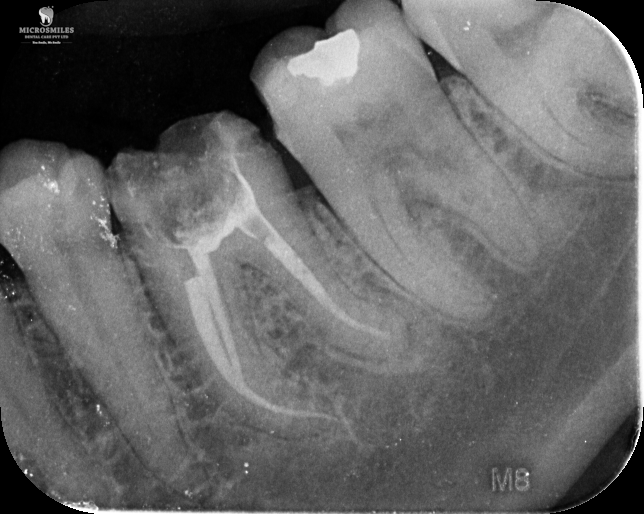

Our treatments are performed using advanced dental microscopes that magnify up to 25x- allowing us to identify previously hidden canals, fractures, or infected areas that standard tools may miss. This level of detail means faster, more accurate procedures and fewer surprises, giving your tooth the attention it truly deserves.

We streamline the retreatment process by using enhanced imaging, digital diagnostics, and precision tools-reducing unnecessary visits and helping you get back to normal faster.